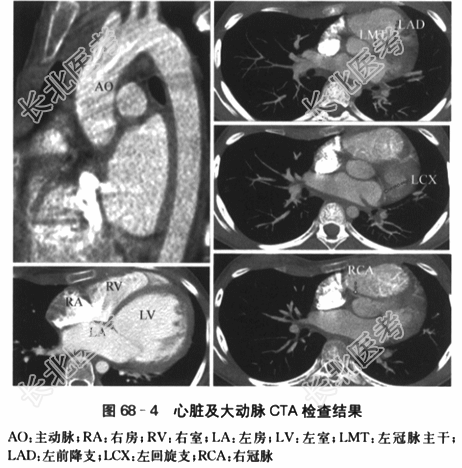

2015年5月18日复查:①左室内径显著增大,LVEDD61mm,LVESD49mm,心功能不全LVEF40%;②左室内占位基本消失;③二尖瓣反流(轻度);④肺动脉高压(轻度)。 (4)24h动态心电图:①窦性心动过速。②单一形态室性早搏1823次/24h,见6对成对出现。③ST-T段改变。④QRS电交替。 (5)心脏及大动脉计算机断层血管造影(CTA):心影增大,左室为著,左室内壁毛糙;主动脉弓未见明显异常;冠状动脉起源未见异常。如图68-4所示。